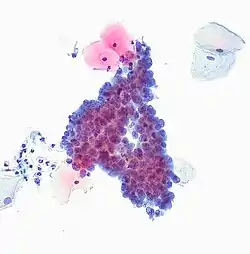

Цитотехнологія (від грец. κύτος, латинізоване «цитос» — порожнина, вмістилище, тут: «клітина», грец. τεχνη — мистецтво, майстерність і грец. λόγος — слово, знання) — мікроскопічна інтерпретація клітини для виявлення раку та інших патологій[1].

Технологія включає в себе вивчення зразків, узятих з шийки матки (див. Тест Папаніколау), легень, шлунково-кишкового тракту або порожнини тіла. Зразки оцінюють фахівці-медики відповідних спеціалізацій. У деяких лабораторіях комп'ютер виконує початкову оцінку, виділивши слайди, області, які можуть становити особливий інтерес для подальшого розгляду. Аномальні зразки для остаточної інтерпретації розглядають фахівці-медики, патологоанатоми[2] .